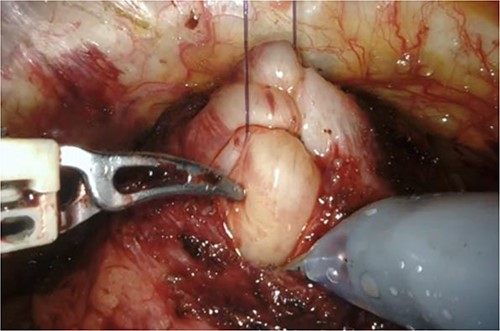

RARP was performed without preoperative hormone therapy. All steps of the RARP procedure were based on a previously established method described by Patel et al. [5], in which all procedures were performed via the transperitoneal approach with a six-port technique. In our patient, we performed conventional RARP. In cases with middle-lobe hypertrophy, prostate dissection around the bladder neck is an important feature. In this procedure, the border between the bladder neck and prostate is dissected using electrocoagulation, and when the middle lobe of the prostate is exposed, it is punctured using a 25-cm, 26-mm, 3–0 monofilament needle and lifted using the fourth arm several times (Fig. 2). The manual procedure, involving pulling in various directions and re-puncturing when the middle lobe is exposed, is repeated until the middle lobe is completely exposed. This reveals the bladder trigone and ureteral orifice and allows identification of the appropriate resection line. At this point of the dissection, the prostate is dissected, the dorsal seminal vesicle is penetrated, and finally, the Denonvilliers fascia is dissected (Fig. 3). Surgery was completed without additional suturing in the bladder neck side. The console time was 2 h 9 min, and the anesthesia time was 3 h 40 min. Bleeding volume was 28.5 ml, including urine volume. The weight of the removed prostate was 70 g. The pathological features were as follows: tumor size 10 × 5 mm (largest tumor layer); Gleason score 4 + 3 = 7; and adenocarcinoma pT2c, ly0, v0, pn0, sv0, EPE0, and RM0. Postoperatively, there were no anastomotic leaks, and no serious complications, categorized as grade 2 based on the Clavien–Dindo classification v2.0, developed.

Puncture of the middle-lobe using a 25-cm, 26-mm, 3–0 monofilament needle.

Grasping of the thread with the fourth arm followed by lifting.